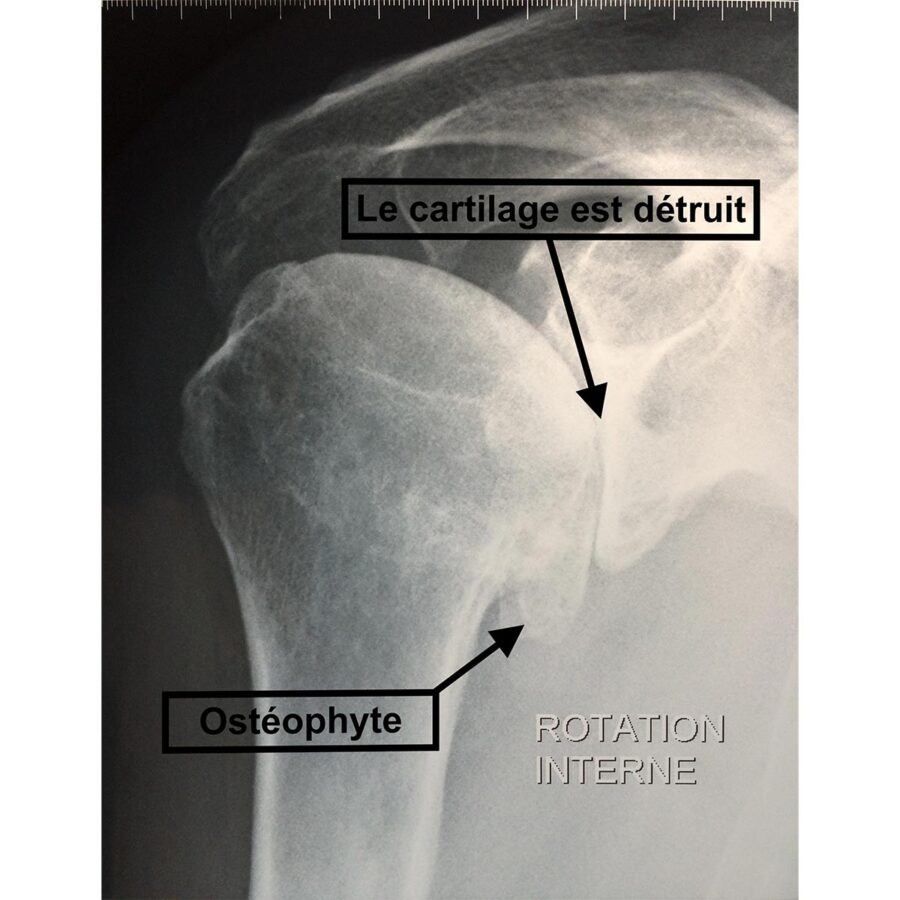

L’arthrose de l’épaule est rare comparativement à l’arthrose du genou ou de la hanche. Elle est localisée au niveau de l’articulation entre la tête humérale et la glène de l’omoplate, elle est appelée omarthrose.

Elle peut être en lien avec le vieillissement naturel des articulations, ou se développer dans les suites de complications à long terme d’une luxation récidivante non stabilisée, d’une fracture ou encore d’une rupture de la coiffe des rotateurs.